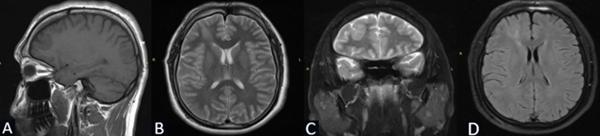

Se solicita RM de cerebro con contraste de cortes de 1 mm donde se objetiva lesión espontáneamente hipointensa en la secuencia T1 localizada en la región frontal derecha entre F1 y F2 de 3 x 2.25 x 2.84 cm. Hiperintensidad de la sustancia blanca subcortical en T2 de forma triangular con base hacia la corteza y vértice hacia la región ventricular (signo del transmanto), engrosamiento cortical focal, pobre delimitación entre la sustancia blanca y gris. Sin efecto de masa y escaso realce tras la administración del contraste (Figura 1).

Figura 1. Caso 1: RM de cerebro. A) Secuencia T1. Corte sagital. B) Secuencia T2. Corte axial. C) Secuencia T2. Corte coronal. D) Secuencia T1 con contraste. Corte axial.